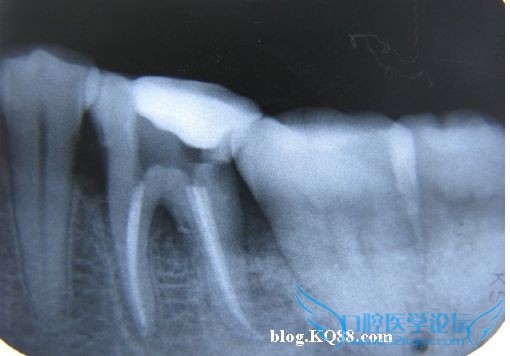

术前X光,可见髓腔基本成一条线了,钙化严重

近中偏位投照

正位投照,由于X光是平面成像,所以必须多角度投照确认,并且只能作为参考